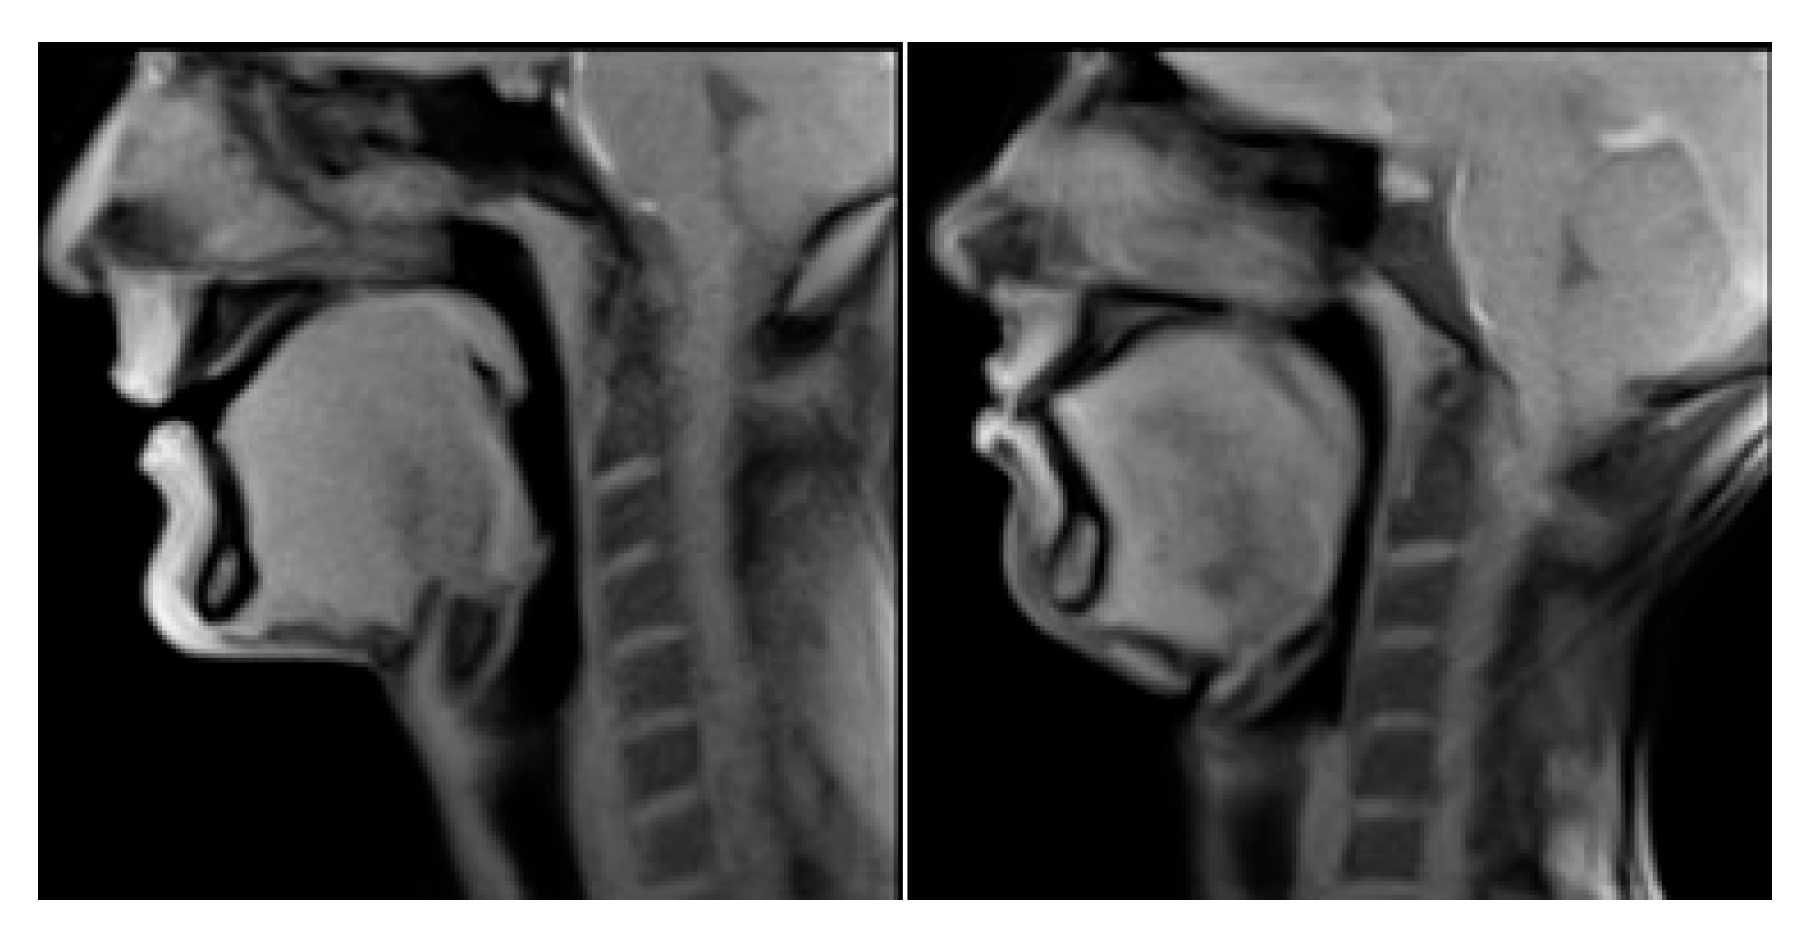

4. Results